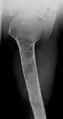

X-ray showing enchondromas localized in the humerus of a 37-year-old patient affected with Ollier disease